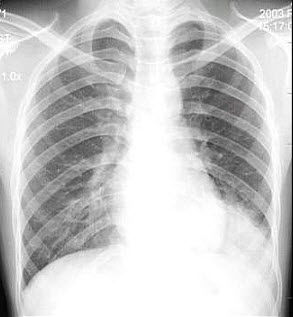

76、单项选择题

男,24岁,低热2周,咳少量痰。胸片示右上肺不均密度增高影,其中有空洞形成,血沉45mm/h。

最可能的诊断是()

A.右上肺炎

B.右上肺结核

C.右上肺癌

D.右上肺囊肿

E.右上肺脓肿